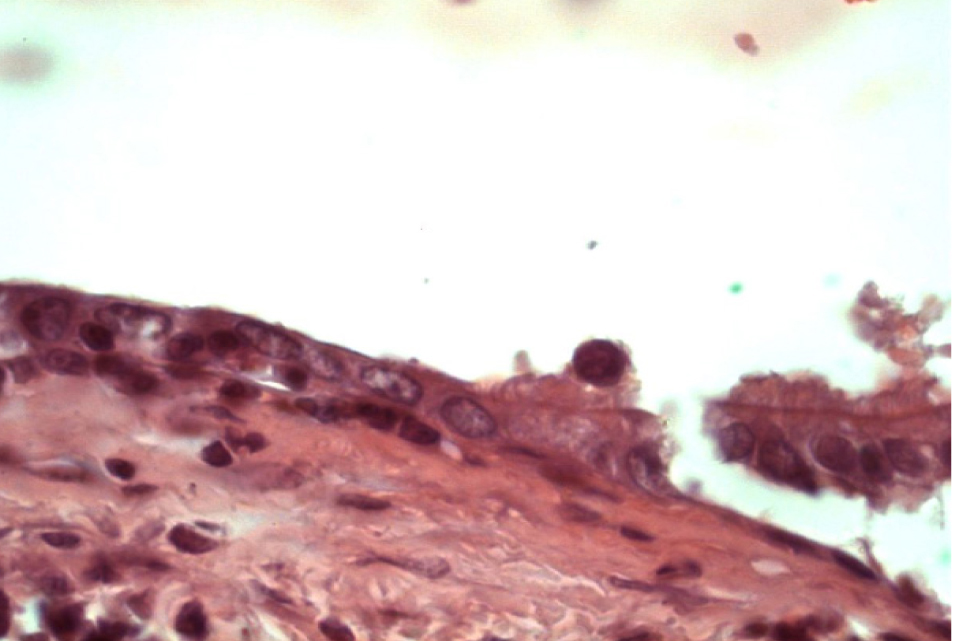

Многорядный мерцательный эпителий бронхов подвергается различным дегенеративным изменениям. Высота эпителиального пласта варьирует. Встречаются участки как плоского, так и кубического эпителия, мерцательные клетки которого содержат немногочисленные реснички (рис. 5).

Рис. 2. Скопление крупных многоядерных макрофагов. Окраска гематоксилином и эозином. Ок. 10. Об. 100. Иммерсия